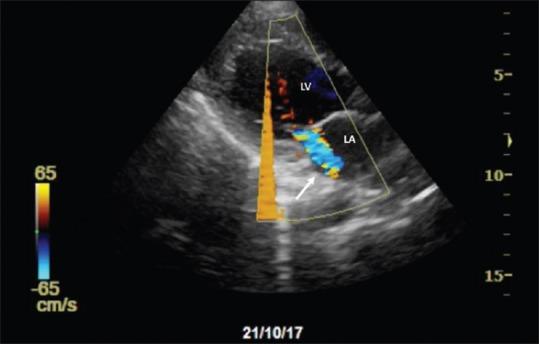

Cardiogenic pulmonary edema usually presents with characteristic clinical features and bilateral infiltrates on the chest radiograph. Rarely, pulmonary edema may manifest unilaterally, leading to a mistaken diagnosis of a primary lung pathology. We present a 30-year-old man who developed acute coronary syndrome following an overdose of alprazolam. He developed breathlessness with unilateral infiltrates on the chest radiograph. Echocardiography revealed regional wall motion abnormalities related to underlying ischemia and acute mitral regurgitation with an eccentric jet. Besides, he had significant impairment of left ventricular systolic function. His coronary angiogram revealed a slow-flow phenomenon in the right coronary and left anterior descending artery territories. Ischemia-related dysfunction of the posterolateral papillary muscle probably led to a floppy posterior mitral leaflet and an eccentrically directed regurgitant jet, leading to unilateral pulmonary edema. He was commenced on dual antiplatelet therapy, heparin infusion, atorvastatin, frusemide, and ramipril, following which he showed gradual clinical improvement along with resolution of the radiological infiltrates. His left ventricular function improved, and the mitral valve function normalized on echocardiography within a week.

心源性肺水肿通常表现为特征性临床症状及胸部X线片显示双侧浸润影。肺水肿很少单侧出现,从而导致误诊为原发性肺部疾病。我们报告一名30岁男性,在过量服用阿普唑仑后发生急性冠状动脉综合征。他出现呼吸困难,胸部X线片显示单侧浸润影。超声心动图显示与潜在缺血相关的节段性室壁运动异常以及伴有偏心反流束的急性二尖瓣反流。此外,他的左心室收缩功能严重受损。其冠状动脉造影显示右冠状动脉和左前降支动脉区域存在血流缓慢现象。后外侧乳头肌的缺血相关功能障碍可能导致二尖瓣后叶脱垂及偏心反流束,进而导致单侧肺水肿。他开始接受双联抗血小板治疗、肝素输注、阿托伐他汀、呋塞米和雷米普利治疗,之后临床症状逐渐改善,放射学浸润影也逐渐消退。一周内,他的左心室功能改善,超声心动图显示二尖瓣功能恢复正常。